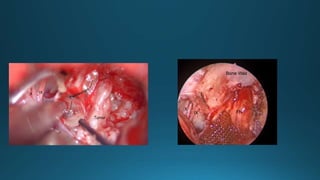

Image source – you tube

,UT southwestern medical

centre .

Cameron c wick, md

Image source – you

tube ,UT

southwestern

medical centre .

Image source

– you tube

,UT

medical

Cameron c

wick, md